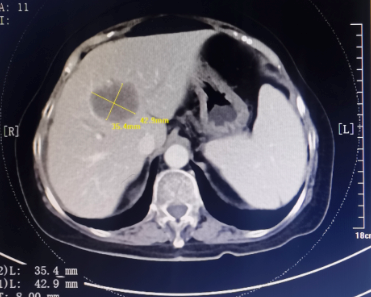

患者为67岁女性,1年余前诊断胃腺癌晚期,肝脏、骨骼及淋巴结多发转移,本次入院复查发现肝脏病灶进展,科主任白俊主任医师、主管医生刘莹主治医师详细分析并与患者家属沟通病情,考虑患者既往接受多线系统性抗肿瘤药物治疗,且治疗过程中多次出现剂量限制性骨髓毒性,继续更换药物治疗的选择空间不多,推荐超声引导下微波消融部分肝脏转移病灶,以期为后续继续免疫及靶向治疗创造在体瘤苗的机会。段宝军副主任医师认真阅片后,考虑该例患者肝转移病灶大(最大径超过5厘米),且毗邻膈肌、肝左静脉及第一肝门等重要结构,因此采用3D可视化手术规划系统设计微波消融方案,在麻醉科常建华副主任医师及手术室的精心配合下,顺利完成了肝转移病灶微波消融手术。

超声引导下肝癌病灶微波消融术微创、经济,且无辐射,是指南推荐的肝癌标准治疗方案。但由于重复进针的人为误差、热传导不足、肝脏储备功能等因素的影响,大肝癌的消融治疗难以做到根治性消融,尤其是危险区域的肝癌病灶微波消融易发生严重并发症,导致超声引导下微波消融的治疗作用与外科手术存在一定差距。

3D可视化系统可通过分析、融合、渲染等处理患者术前增强MRI或CT影像数据,在系统上创建不同的模块(如正常肝、病肝、门静脉、肝静脉等模块),对肝内外胆管及动、静脉系统重建,分析病灶与周围重要器官的关系,以及可能损伤的结构,确定安全边界,模拟进针路径、针数、消融时间,计算肿瘤体积、剩余肝体积,用不同颜色代表进针次序,对较大肿瘤需不断调整针的空间位置使热场范围能够覆盖安全边界。该技术辅助超声引导下肝癌微波消融术可提高消融成功概率、有利于制定更加合理的手术方案,减少消融手术并发症的发生,为肝癌的精准、安全消融治疗提供了新的选择。